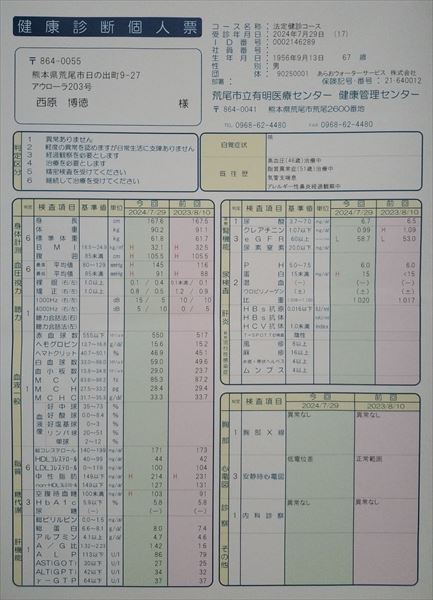

0140 健康診断結果

0109 24.7.29健康診断=pdf

0108 ①22.8.23荒尾市民病院=pdf ②2023-08-21健康診断結果.pdf 8/10(木)受診 荒尾市民病院